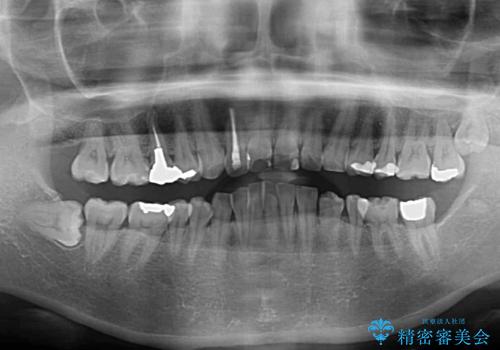

- 前歯のデコボコと前方に斜めに飛び出した前歯を気にして来院された患者様です。

口元の突出感はあまり気になっていませんでしたが、上下の前歯の前後差が大きかったため、上顎左右の第一小臼歯を抜歯し、上顎が裏側装置であるハーフリンガルにて矯正治療を行うこととしました。

咬合力が非常に強く、スペースがなかなか閉じなかったことと、上下の正中が著しくずれてきてしまったため、下顎左側小臼歯を途中抜歯することとなりました。